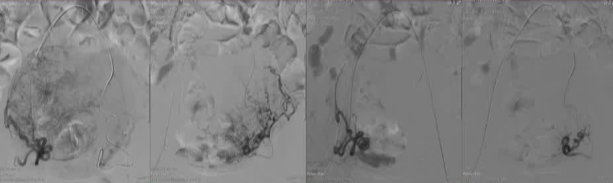

可降解的基于明胶的亲水性校准型 Nexsphere 微球。平均使用2.5安瓶 500-700μm,使用5安瓶 700-900

进行了有目的性的单侧6例或双侧20例栓塞手术。

基于术前的磁共振成像特征以及血管造影信息

双侧子宫动脉栓塞,右侧1安瓶 500-700μ吗,左侧4安瓶500-700μm +7安瓶 700-900μm 可吸收微球 |